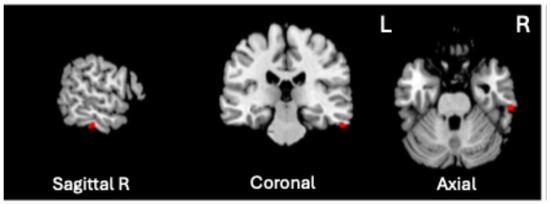

As a preliminary analysis, we conducted a structural VBM-GMV analysis on 74 SZ patients and 91 healthy controls. No significant effects of clinical covariates (i.e., age of onset, illness duration, and medication) on the whole-brain VBM-GMV values in SZ patients were found. A significant between-group difference (HC > SZ, i.e., GMV atrophy in patients) was observed, with t = 4.39, p = 0.00001 (FDR-corrected q < 0.001), Cohen’s d = 0.688. Figure 1 shows the significant GMV atrophy found in the brains of SZ patients, and Table 2 lists the corresponding MNI coordinates.

Figure 1.

Significant GMV atrophic regions in SZ patients compared to HCs (q < 0.001).

A significant positive association was found between VBM-GMV and Generalized Psychopathology scores only (t = 4.72, p = 0.0000057, q < 0.01, volume size = 82 mm3; Cohen’s d = 1.112). As shown in Figure 2, the greater the severity of Generalized Psychopathology, the greater the GMV in the right inferior temporal gyrus (ITG), corresponding to Brodmann Area (BA) 20 (MNI coordinates 61, −26, −28).

Significant positive association between the VBM-GMV in the right inferior temporal gyrus (ITG) and the severity of Generalized Psychopathology PANSS subscale in SZ patients (q < 0.01).